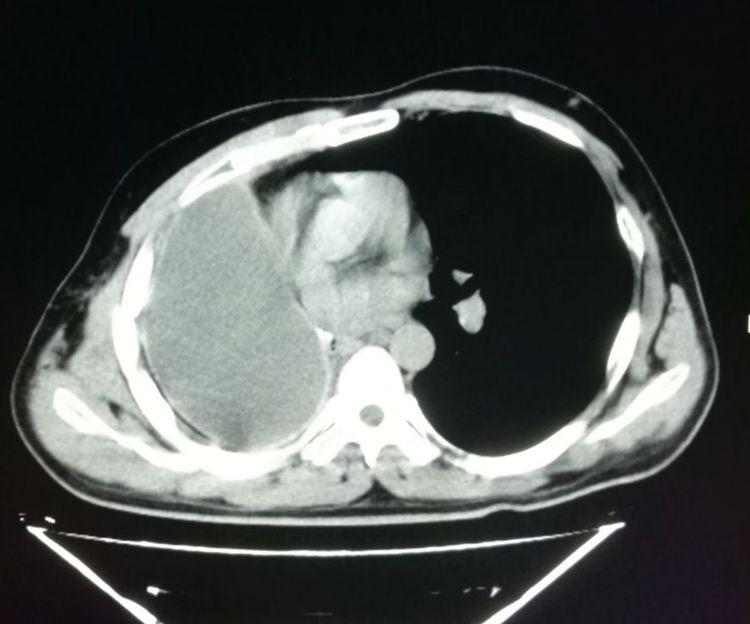

而到今年已经是第7个年头了,最近一次的复查依然良好:

并且我们可以看到,在残腔的周围,已经发生了斑点状的胸膜钙化(白色斑点状影)。

我们上面提到过,随着时间的推移,边缘胸膜可以发生钙化,这一点是吻合的。

这也是一位幸运的老人。